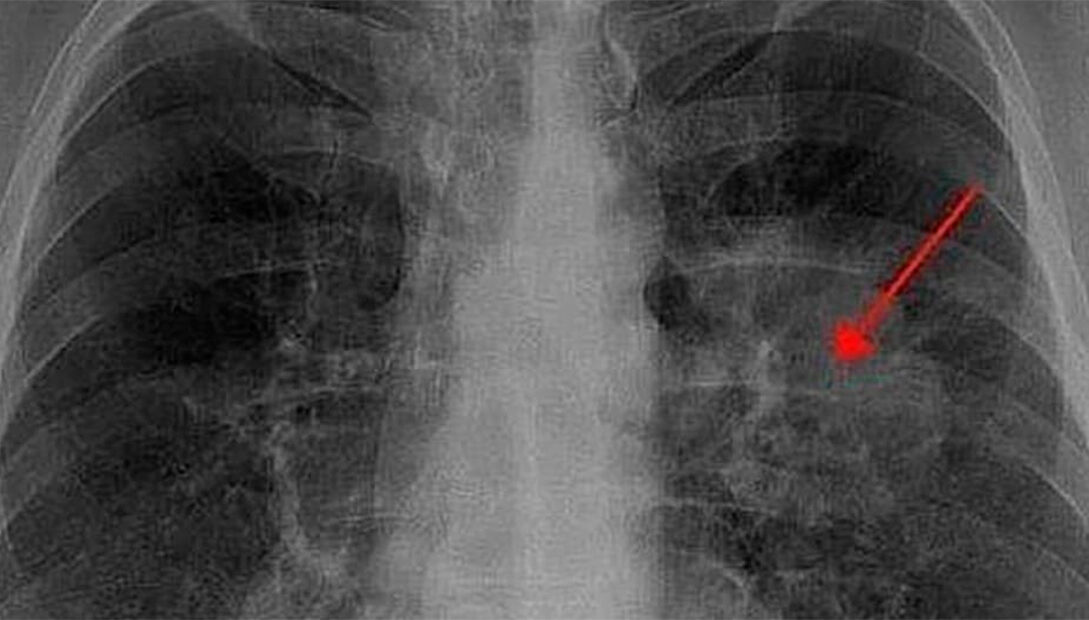

Cáncer de pulmón: principal causa de muerte por cáncer en México y el más letal

El cáncer de pulmón ocupa el séptimo lugar en incidencia en México, pero es el tumor más letal, siendo la primera causa de muerte por cáncer en el país. Según Horacio Tovalín Ahumada, académico de la FES Zaragoza de la UNAM, la incidencia de este tipo de cáncer va en aumento, especialmente entre mujeres, quienes en ocasiones fuman más que los hombres.

• Diagnóstico en fases avanzadas: 80% de los casos son detectados en etapas tres o cuatro, cuando el tratamiento ya no es curativo, sino paliativo.

• Pronóstico crítico: En México, se registran aproximadamente 9 mil casos nuevos al año, y el 80% de estos tienen un desenlace fatal en un plazo de seis meses.